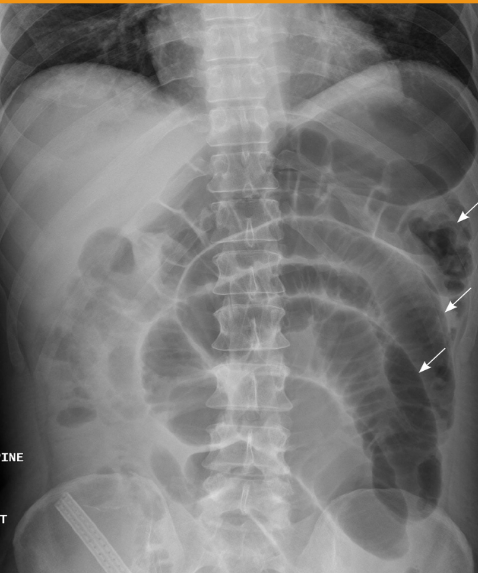

What abnormality is visualized?

Small Bowel Obstruction (SBO) bc larger than normal